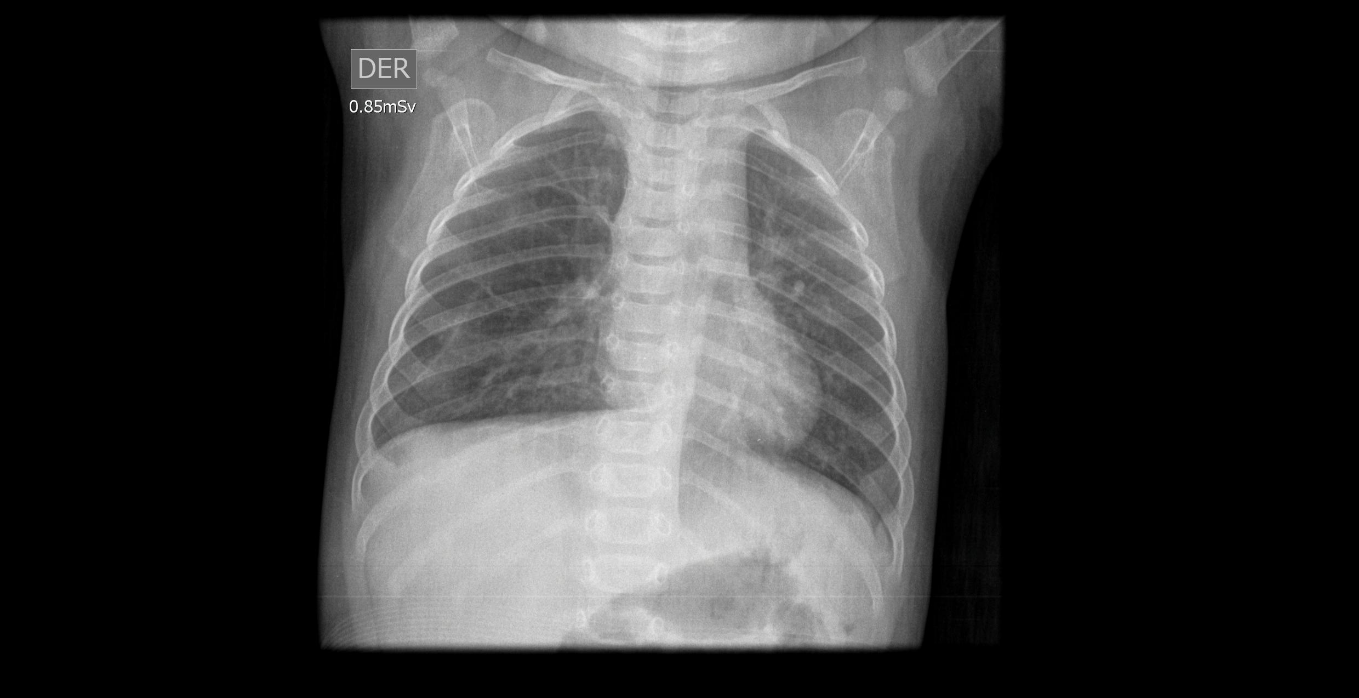

Caso pediatría

lunes, 1 de octubre de 2018